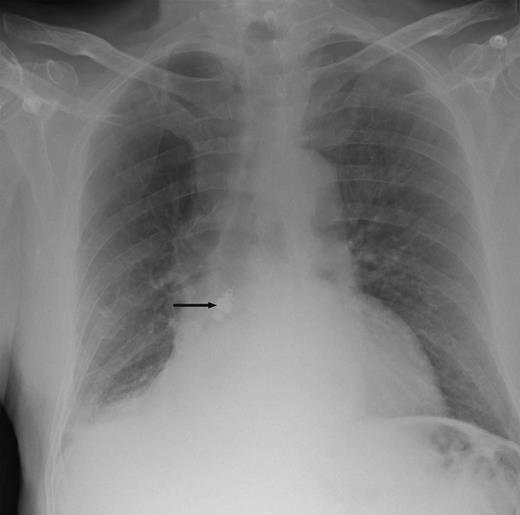

Chest X-ray (Fig. 1) and computed tomography (CT) scan (Fig. 2) revealed a foreign body in the right bronchus intermedius with collapse and consolidation of the distal bronchial tree. The gentleman was transferred to the cardiothoracic unit. An adult Negus rigid bronchoscope introduced under general anaesthesia revealed a metallic foreign body with smooth rounded contours wedged in the bronchus intermedius. This was removed using a Wolfe lighted grabber. The foreign body was a capsule endoscope (Given Imaging Limited, Israel) (Fig. 3).

Chest X-ray showing a metallic foreign body impacted in the right bronchus with collapse of the middle and lower lobes on the right side.